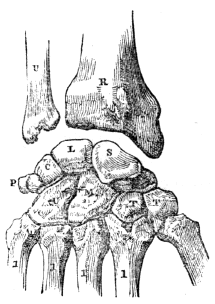

Fig. 15.

Fig. 15. U, The ulna. R, The radius. S, The scaphoid bone. L, The semilunar bone. C, The cuneiform bone. P, The pisiform bone. These four form the first row of carpal bones. T, T, The trapezium and trapezoid bones. M, The os magnum. U, The unciform bone. These four form the second row of carpal bones. 1, 1, 1, 1, 1, The metacarpal bones of the thumb and fingers.